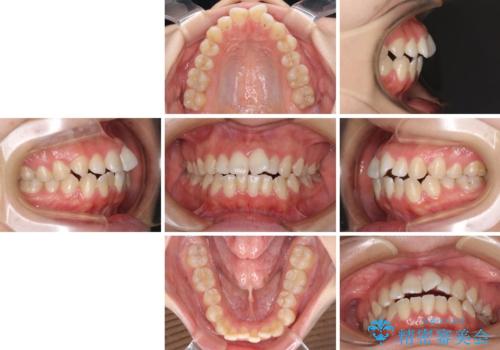

- 前歯の上下スペースによる食べにくさを気にして来院された患者様です。

インビザラインにより上下の前歯の隙間を閉じていくこととしました。

前歯のデコボコの解消と並行して上下の奥歯を圧下させるようにすることで、前歯を接触させるように計画しました。

上下の隙間に舌が入り込むことがオープンバイトの原因であったため、舌の筋肉のトレーニングも並行して行い、後戻りの抑制を図りました。